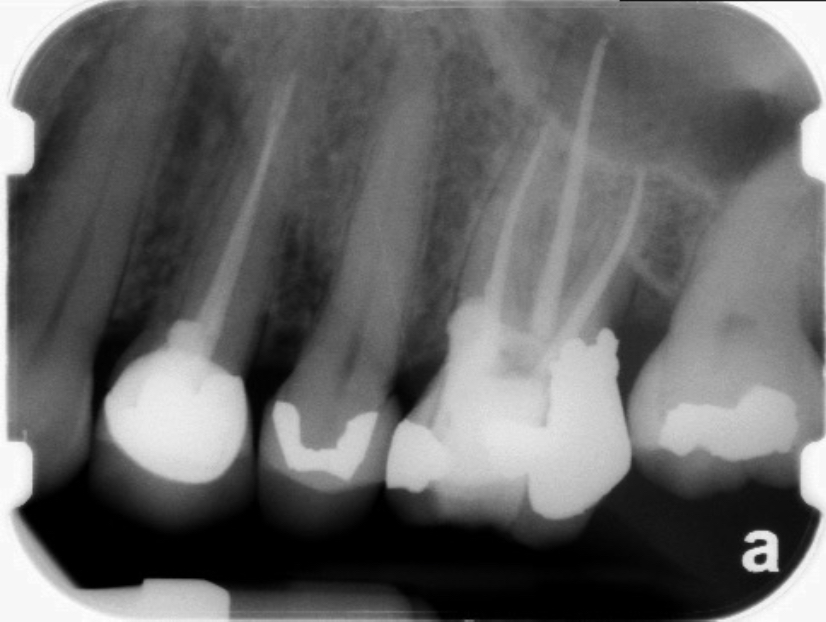

Clinical procedure: Once a perforation occurs, the extent of the perforation must be assessed. If there is an adjacent bony defect, the bony defect should first be filled with an osteoconductive or osteoinductive material. This can be done with a bone graft, calcium sulfate, or collagen/gelatin sponge. The dentinal portion of the tooth that has been perforated is then restored with MTA (Figure 9 through Figure 14).

Fig 9 Preoperative radiographs showing mesial perforation.

Figure 9

Fig 10. Preoperative radiographs showing mesial perforation.

Figure 10

Fig 11. MTA perforation repair done, and calcium hydroxide medication placed in the canals.

Figure 11

Fig 12. Postoperative radiograph.

Figure 12

Fig 13. 2-year follow-up radiographs showing the positive outcome.

Figure 13

Fig 14. 2-year follow-up radiographs showing the positive outcome.

Figure 14